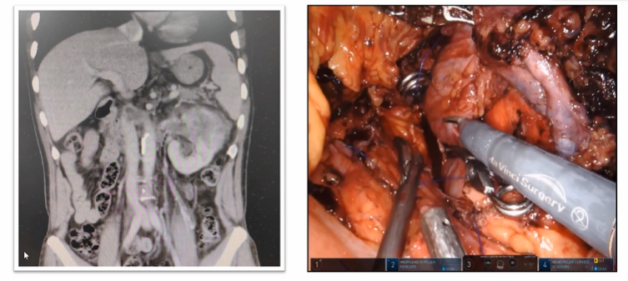

既往手术切除肾脏我们通常都会先处理肾动脉,但事实上有相当一部分患者可以先切断下腔静脉,再处理肾动脉,这样的病例在临床中也比较常见。如下图所示,当患者瘤栓充满血栓后,没有很好的空间去寻找肾动脉,此时我们可以先离断下腔静脉,这样就有足够的空间,再去取瘤栓和切断肾动脉就会变得简单便捷。当前这种模式本科室也已成为一种常规的术式,通过这种方式可以简化手术步骤,同时也可以很好地处理掉肾动脉。

如下图所示,该病例瘤栓充满整个下腔静脉,同时长满血栓,对于该病例我们采用全封闭式的En-block切除,首先是离断下腔静脉,翻起来以后去找寻右肾动脉,切断右肾动脉以后再把左肾静脉切断,然后一直沿着瘤栓向肝后寻找游离肝门后方腔静脉。既往类似病例中肝门后方腔静脉很难暴露清楚,但是有了机器人助力,使其充分显露出来就变的相对容易很多。肝后下腔静脉经过充分游离后,再将瘤栓全部挤压进入腔静脉中,然后探查至无瘤栓处,直线切断腔静脉,将瘤栓取出。完全封闭式的瘤栓取出,可以获得很好的操作空间。该病例曾在2023年4月在第8届泌尿生殖系统研讨会上进行演示。